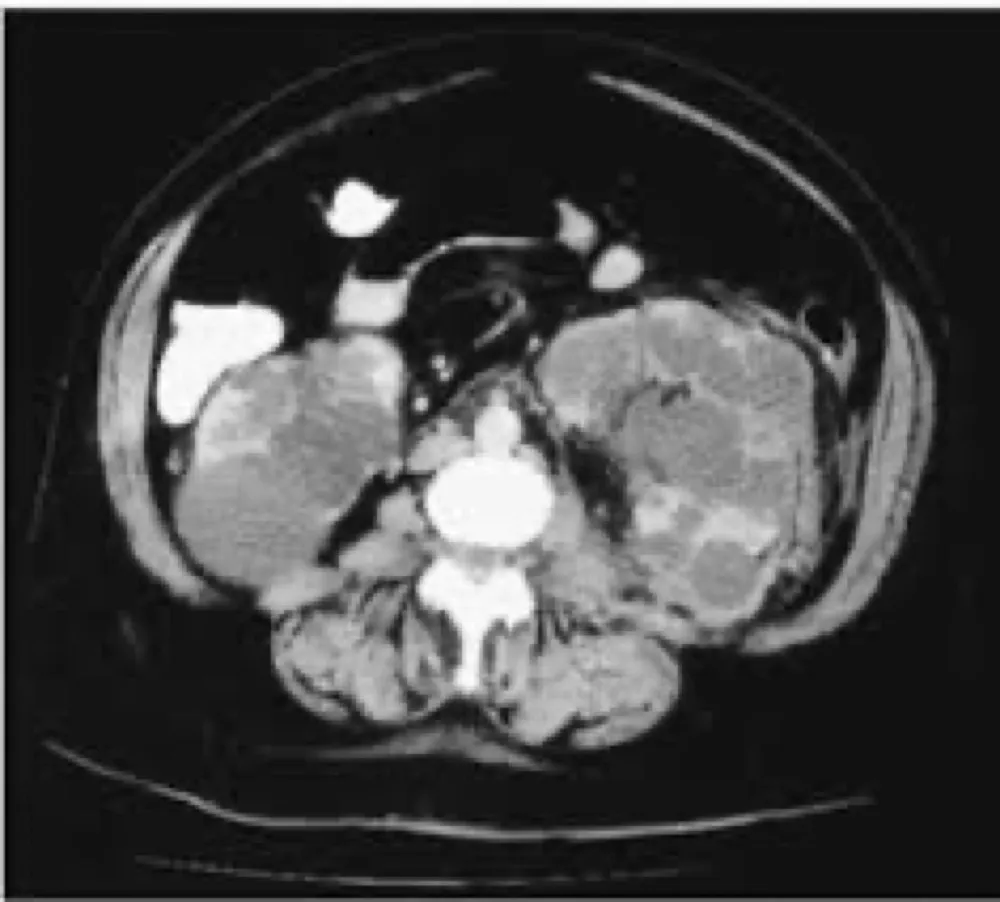

Diálise Peritoneal na Doença Renal Policística: existe algum motivo para não indicar?

A DRPAD não é contraindicação à DP — e, na prática, muitos pacientes têm resultados comparáveis à hemodiálise. O “porém” está na mecânica: rins/hepatomegalia podem reduzir tolerância a volumes, aumentar risco de hérnias e extravasamentos, e piorar desconforto respiratório. Com técnica adequada (cateter presternal ou lateral, volumes menores, cicladora noturna e decúbito supino), a maioria das barreiras é contornável. Neste post, revisamos quando a DP é ótima, quando exigir cautela e como ajustar a prescrição para segurança e qualidade de vida.